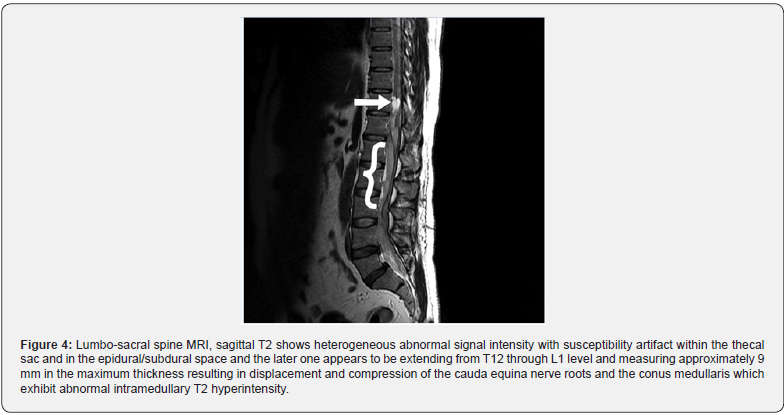

An urgent spine CT scan was done, which did not show any evidence of collection. Twenty-four hours after developing his spine symptoms, the patient had a spine MRI revealing heterogeneous abnormal signal intensity within the thecal sac and in the epidural space extending from T12 down to L1; measuring approximately 9 mm in the maximum thickness resulting in displacement and compression of the cauda equina nerve roots and the conus medullaris which exhibited abnormal intramedullary T2 hyperintensity (Figures 3-5). The overall appearance was highly suggestive of intraspinal hematoma with different stages of hemorrhagic degradation products.

The patient developed iatrogenic complications related to lumbar drain removal while on aspirin, clopidogrel, and heparin infusion, although the procedure was not traumatic. Nevertheless, his initial symptoms on presentation did not improve and became completely blind and paralyzed. With this new emerging complication, the neurosurgical team was consulted for urgent hematoma evacuation. The patient underwent an urgent lumbar laminectomy at T11, T12, and L1 with hematoma evacuation. Intra-operatively, the neurosurgeon noted suspicious abnormal vessels at conus medullaris with the possibility of an AV (arteriovenous) malformation, which may have contributed to the hematoma formation on the background of uninterrupted antiplatelet agents and anticoagulation. Therefore, the dura was kept open within the spinal space to prevent the hematoma’s recollection, and the patient had wound drainage. In few days following the spinal surgery, the patient vision started to improve. However, we remained unsure of the exact mechanism that improved the patient’s vision, as he was fully anticoagulated on immunosuppressant agents and acetazolamide. Additionally, the dura was kept open within the spine, and he had optic nerve sheath fenestration. What remained as a question is whether he has CNS vasculitis and whether or not he needs a cerebral angiography to document that? This patient had coronary vasculitis in the past that caused acute coronary syndrome. Will finding CNS vasculitis change our management as the patient was planned to receive plasma exchange, but we delayed when he developed the acute spinal cord syndrome? We discussed the option of doing a cerebral angiography with the patient, but as he had an eventful and complicated hospital course, he did not want to undergo another procedure. So, the decision was not to do it, and he was planned for aggressive immunosuppression by the rheumatology team.